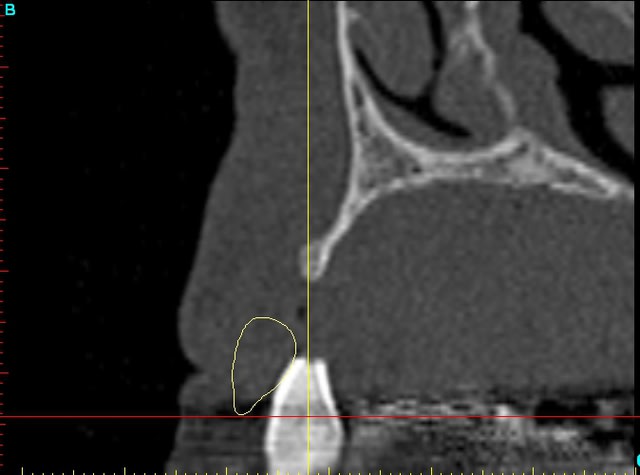

Dar12 dmdcf3 - Eugenol

12dar ujxzdu - Eugenol